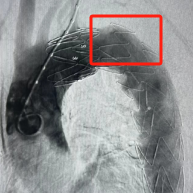

仅通过在右下肢、左上肢两个部位打“针孔”便完成了手术。术后患者当天拔出气管导管、恢复意识,再次复查主动脉CT提示降主动脉支架形态、位置良好,原瘤体隔绝良好。术后仅三天后患者便康复出院。

支架的精准定位释放也十分重要。患者的降主动脉瘤距离左锁骨下动脉非常近,支架过高则影响左锁骨下动脉的血流,支架过低则不能实现良好的隔绝效果。术中凭借多角度造影及精湛的技术,支架释放精确,实现了“两全”。